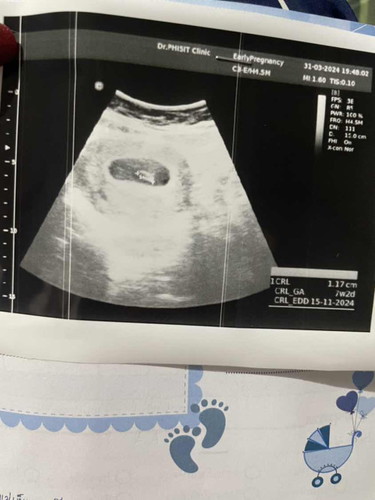

แม่ๆเจอหัวใจน้องกี่วิคกันค่ะ ถ้านับจากประจำเดือนคือ 9 w แต่ในใบซาวน์ ขึ้น 7 W 2 d แม่บ้านนี้ไปซาวน์เมื่อวานเจอถุงตั้งครรภ์ แต่ยังไม่เจอเสียงหัวใจน้อง คุณหมอบอกว่าน้องยังเล็ก อีก 2 อาทิตย์คุณหมอนัดอีกค่ะ แม่กังวลมากเลยค่ะ

ของเรา 6 วีคค่ะ ถ้านับตาม ปจด.ได้ 8 วีค แต่อัลตร้าซาวด์แล้วหมอบอกน้องแค่ 6 วีค ดูจากขนาดตัว ขนาดถุงตั้งครรภ์ วันนั้นที่ไปฝากก็ได้ฟังเสียงหัวใจเลยค่ะ แต่เบามาก หมอต้องเร่งเสียงขึ้นแรงๆให้เราฟัง แล้วก็ในก้อนตัวอ่อนจะมีหัวใจกระพริบๆอยู่ค่ะ ดูจากหน้าจออัลตร้าซาวด์

คล้ายๆเราเลยค่ะนับตามประจำเดือนตอนแรก9+5วีคพอซาวด์8+4วีคในยินเสียงหัวใจแล้วค่ะแต่ก่อนหน้าตอน6วีคไม่เจออะไรเลยค่ะ

เป็นเหมือนกันค่ะ ตอนไปหาหมอครั้งแรก 7week2day ไม่เจอหัวใจน้องค่ะ แต่อีก2อาทิตย์ไป เจอหัวใจค่ะ ตอนนี้ 34 week ค่ะ